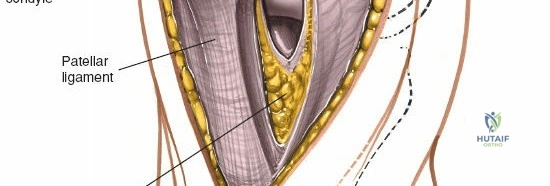

The extensor mechanism comprises the quadriceps femoris muscle group, the quadriceps tendon, the patella, the patellar tendon (ligament), and its insertion into the tibial tubercle.

* Patellar Tendon: Connects the patella to the tibial tubercle.

3. Medial Parapatellar Arthrotomy (Capsular Incision)

This is the defining step of the approach.

* The incision through the joint capsule and retinaculum begins proximally, extending through the medial aspect of the quadriceps tendon.

* It then follows the border between the vastus medialis obliquus (VMO) and the patella, curving distally along the medial border of the patella.

* The incision continues distal to the patella, medial to the patellar tendon, into the synovium and capsule.

* The extent of the proximal and distal incision depends on the required exposure. For TKA, it is typically extended well into the quadriceps tendon proximally and to the tibial tubercle distally.

The medial retinaculum and vastus medialis obliquus are exposed. The proposed capsular incision along the medial patellar border is outlined.